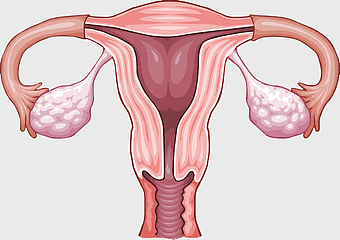

female anatomy diagram, human organ system chart, woman's body structure, female internal organs, human anatomy illustration, medical educational image, anatomical reference guide -

female reproductive anatomy, menstrual cycle illustration, ovarian health diagram, uterus and ovaries visual, gynecological health image, reproductive system education, human fertility chart -